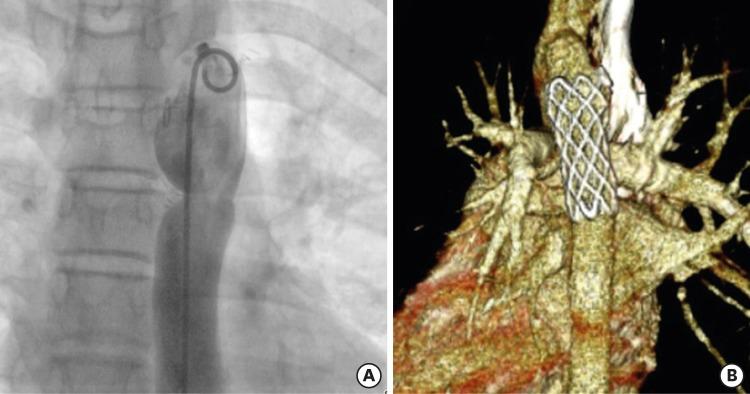

Nine self-expandable stents were implanted in the pulmonary artery, 2 stents in the right ventricle to the pulmonary artery conduit, and 1 stent in the coarctation. The narrowest diameter of the stented vessel increased from 5.7±3.2 mm to 12.6±3.4 mm (p<0.05). The mean pressure gradient across the stenotic lesion decreased from 23.0±28.2 mmHg to 3.2±3.6 mmHg (p<0.05). Distal migration of the stent occurred in 1 patient, and significant neointimal ingrowth was noted in 1 patient.

9个自膨胀支架植入肺动脉,2个支架植入右心室至肺动脉管道,1个支架植入缩窄部位。置入支架血管的最窄直径从5.7±3.2 mm增加到12.6±3.4 mm(p<0.05)。狭窄病变两端的平均压力阶差从23.0±28.2 mmHg降至3.2±3.6 mmHg(p<0.05)。1例患者发生支架远端移位,1例患者出现明显的新生内膜增生。